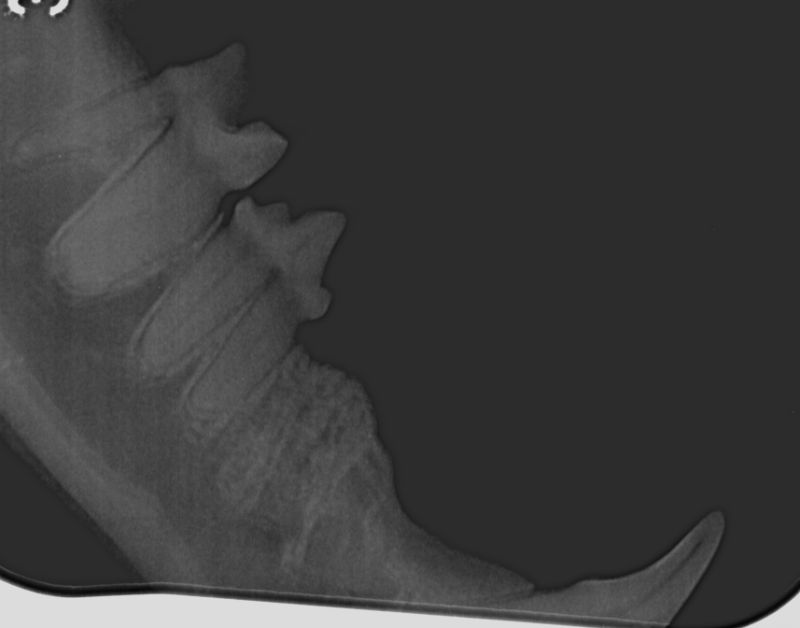

We like to avoid removing teeth where possible, and have a state of the art dental xray so we can check the health of the teeth below the line. This provides us with more information than just the visual appearance, giving us more opportunities to save the teeth!